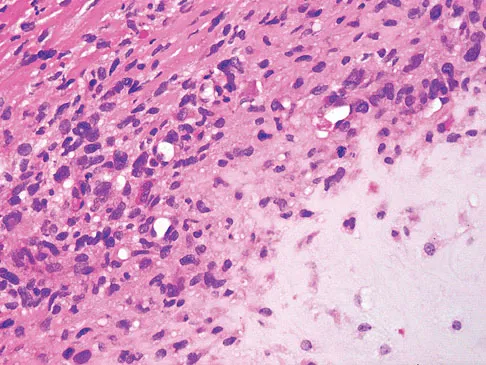

Figures 61a and 61b show the CT and MRI scans of a 40-year-old man who has hip pain. He undergoes total hip arthroplasty and curettage and cementation of the lesion as shown in Figure 61c. Histopathologic photomicrographs of the curettage specimen are shown in Figures 61d and 61e. What is the best course of treatment?

The definitive surgery would be removal of the entire resection bed, and in this case of dedifferentiated chondrosarcoma, a hemipelvectomy was performed. The MRI and CT scans show an aggressive cartilage lesion. The histology, representative of a dedifferentiated chondrosarcoma, shows a bimorphic low-grade cartilage lesion with high-grade spindle cell sarcoma. The cartilage lesion is usually an enchondroma or low-grade chondrosarcoma. The dedifferentiated portion is typically a malignant fibrous histocytoma, osteosarcoma, or fibrosarcoma. Weber KL, Pring ME, Sim FH: Treatment and outcome of recurrent pelvic chondrosarcoma. Clin Orthop Relat Res 2002;397:19-28.